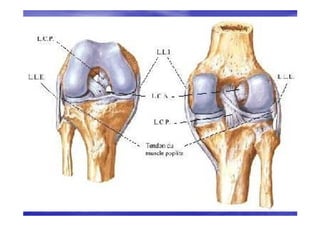

MOYENS D’UNION

LIGAMENTS PASSIFS

Les ligaments passifs

Le système collatéral

(les ligaments latéraux

• Ils assurent la stabilité

Le ligament latéral interne

(collatéral médial) .

Le ligament latéral externe

(collatéral latéral)

Le pivot central

(les ligaments croisés)

Le pivot central (les ligaments

croisés)

antéro postérieure du

genou.

• Leur lésion entraîne le

mouvement du Tiroir,

Tiroir,

recherché cliniquement.